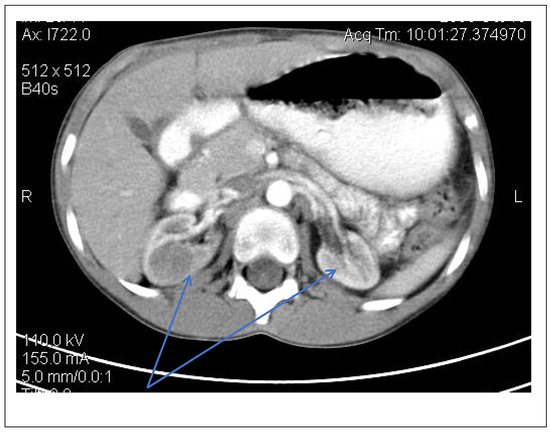

Chest X-ray (Figure 7)

accentuated pulmonary pattern and a heart with an increased transverse diameter

Figure 7. Chest X-ray.

Forty-six days after admission, the patient suddenly complained one morning of epigastric pains, nausea and palmo-plantar burning, associated with a hypertensive episode (BP 180/110 mmHg), for which reason a hemodialysis session was performed urgently, extracurricular. In the same evening, at a BP value of 160/100 mmHg, at rest, the patient presented a sudden and severe worsening of the general condition, dyspnea with orthopnea, intense wheezing, SaO2 89–91%, tachycardia 140/min, subcrepitants disseminated on both lung areas. The suspicion of cardiogenic acute pulmonary edema was confirmed by imaging (chest X-ray—Figure 7, Table 1). Electrocardiographic evaluation (Figure 8, Table 1) revealed subendocardial myocardial ischemia, and echocardiography revealed acute dilation of the left heart, as well as a fine pericardial reaction, 3 mm, without signs of cardiac tamponade (Figure 9, Table 1). At that moment, we made 2-h ultrafiltration, during which the signs of acute pulmonary edema subsided. After 60 min an increase in blood pressure up to 160/120 mmHg is noted, with the maintenance of negative T waves on the monitor. Hemodialysis was stopped and iv Nicardipin was administered, with good results.